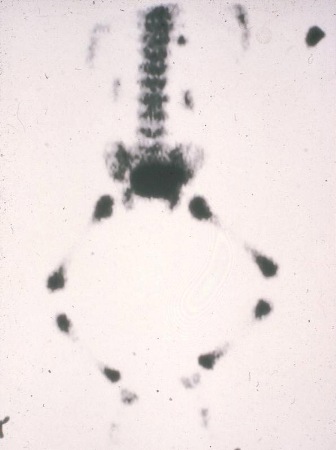

With normal variants, investigation is required if changes are progressive, non-resolving beyond the expected ages, asymmetric or painful; if they cause a functional limitation, a regression or delayed gross motor milestones; or if other abnormalities are observed on musculoskeletal or neurological examination. Investigations may include full blood count/film, acute phase reactants, infection screen, and imaging (x-rays, ultrasound and MRI). Bone scan is rarely indicated in the assessment of acute limp, but may be considered in the assessment of suspected benign or malignant bone cancer.[29][30]

A skeletal survey may be useful in the evaluation of skeletal dysplasia or non-accidental injury. Local policies should be followed. It should be reviewed by an expert radiologist to distinguish changes from normal variants.[Figure caption and citation for the preceding image starts]: Non-accidental injury with 'hot spots' on bone scan due to multiple fracturesFrom Dr Foster's personal collection; used with permission [Citation ends].